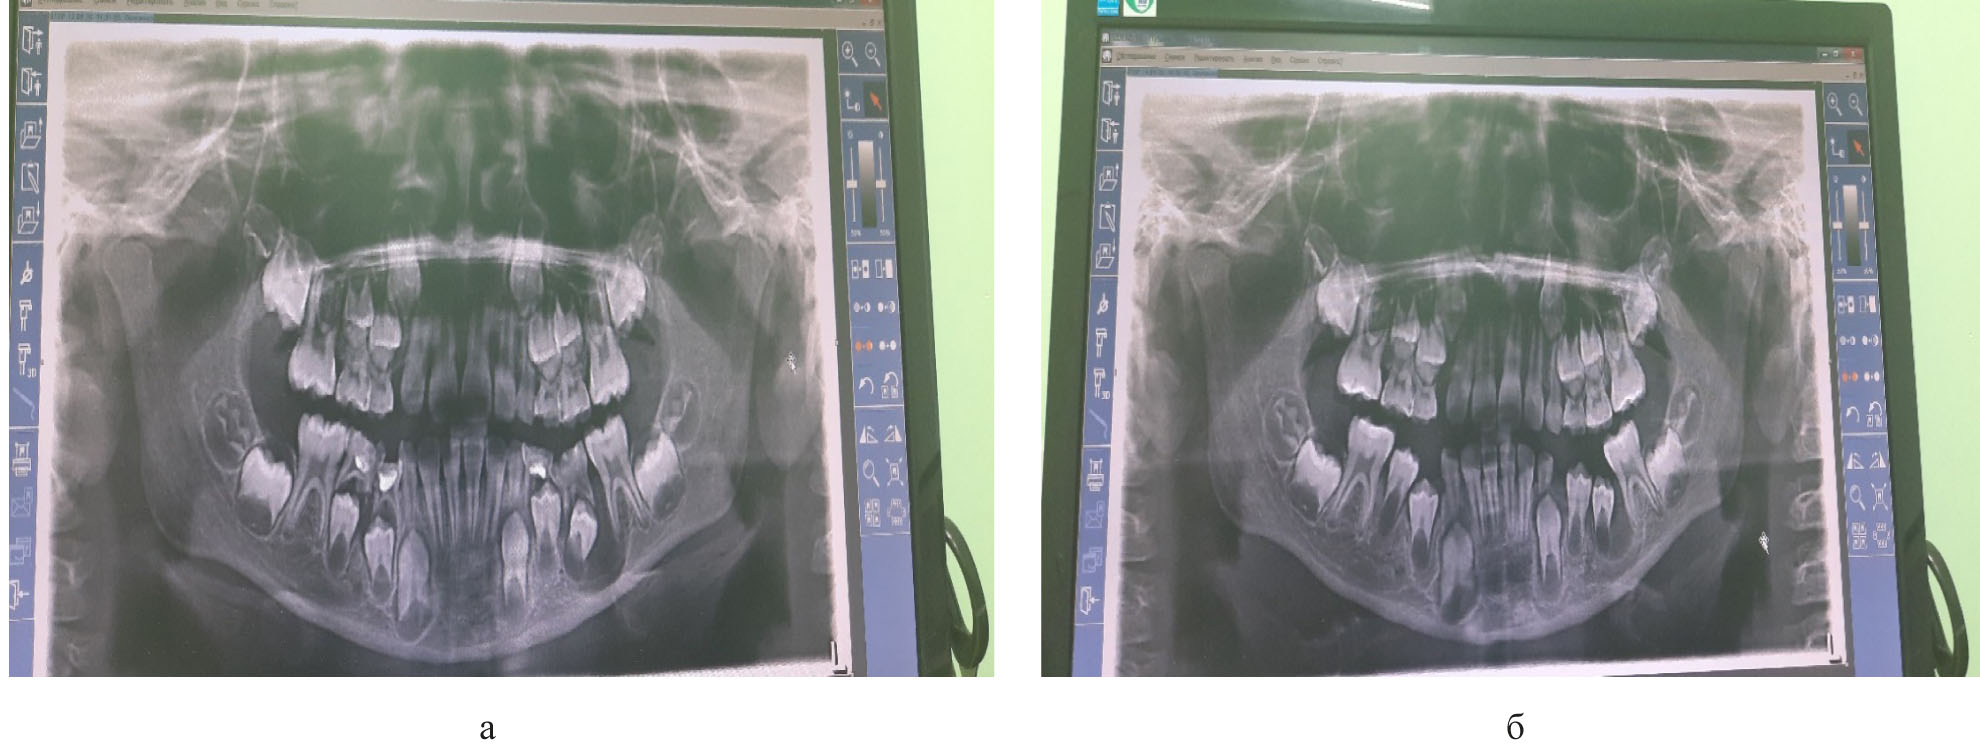

На рис. 5 представлены ортопаномограммы пациента, лечение которого выполнялось модифицированным методом цистостомии.

Рис. 5. ОПТГ пациента: а) до лечения; б) через 3 месяца